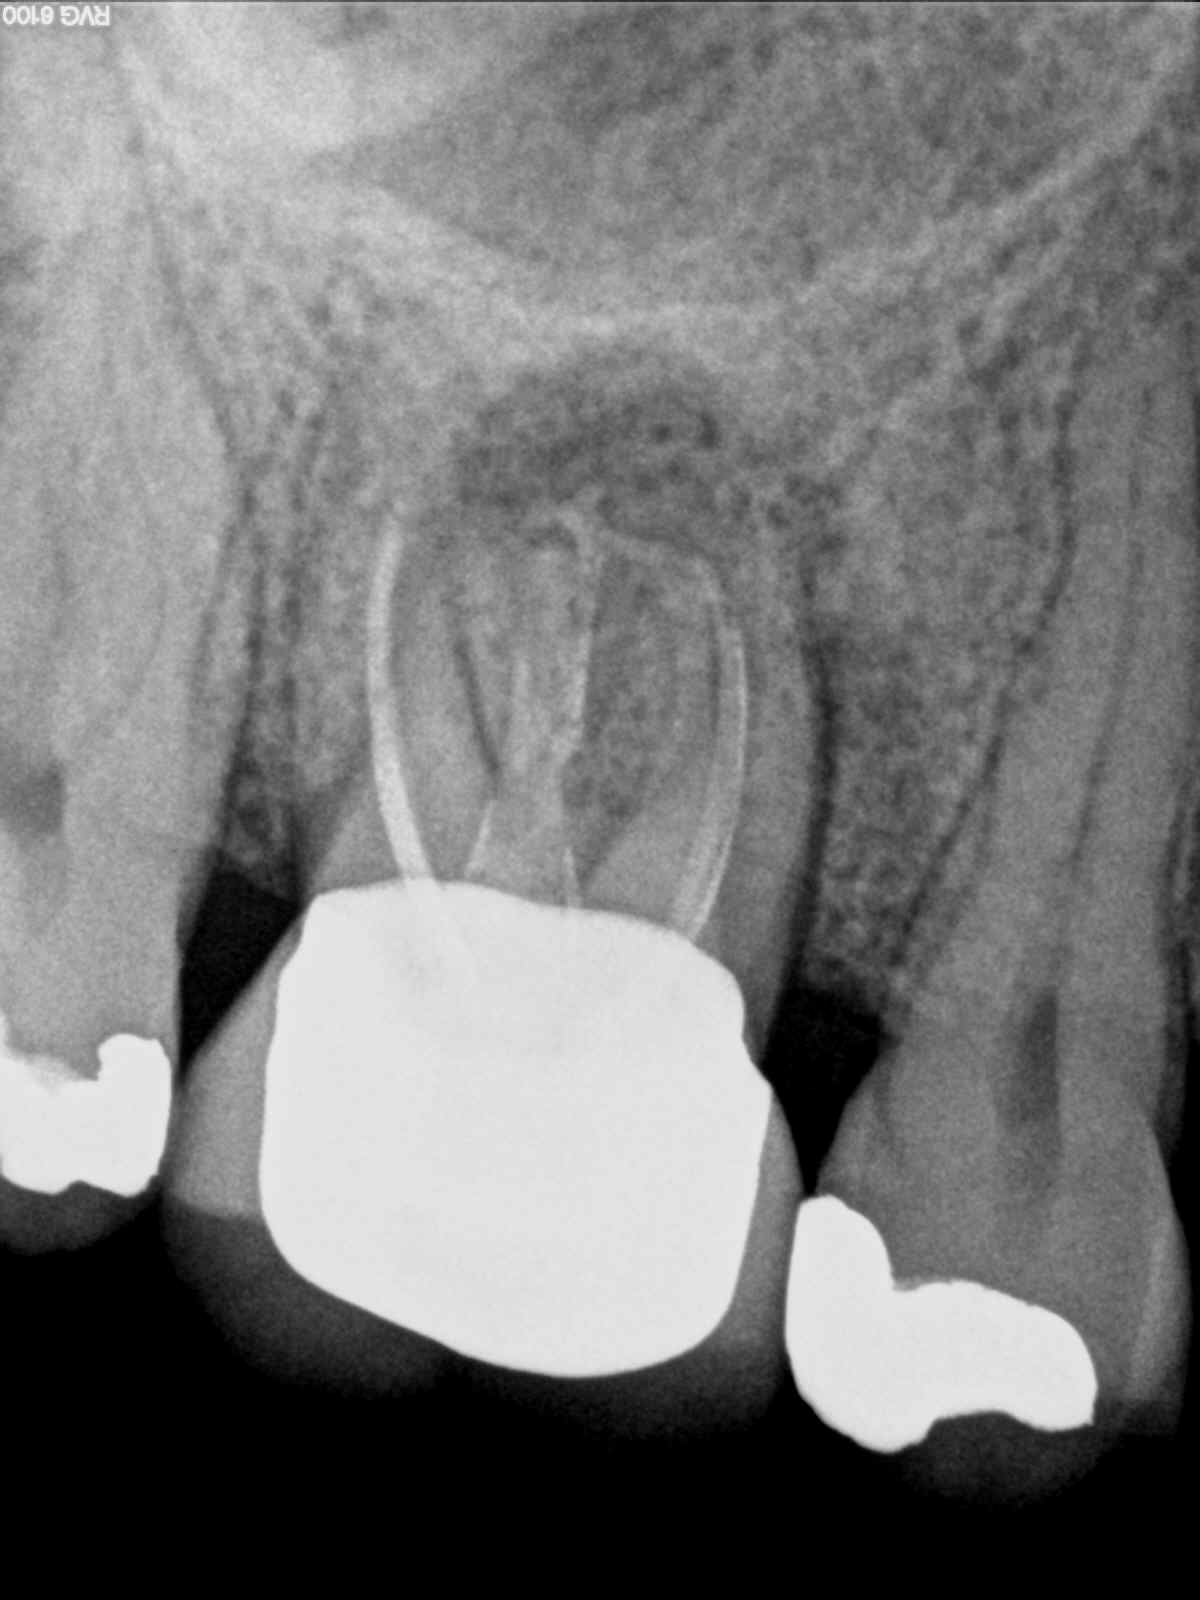

2D vs. 3D – Diagnostische Erleuchtung